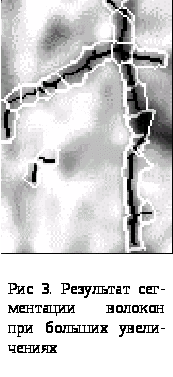

При больших увеличениях толщина протяженных объектов начинает играть существенную роль, поэтому для этого случая был разработан отдельный алгоритм сегментации. Особенность алгоритма заключается в наличии двух параллельных ветвей: обработка самого изображения и его градиента. В результате утоньшения градиента изображения получаются области для обработки, соответствующие либо фону, либо объекту. По соответствию полученного скелета изображения областям определяются протяженные объекты (рис 3).